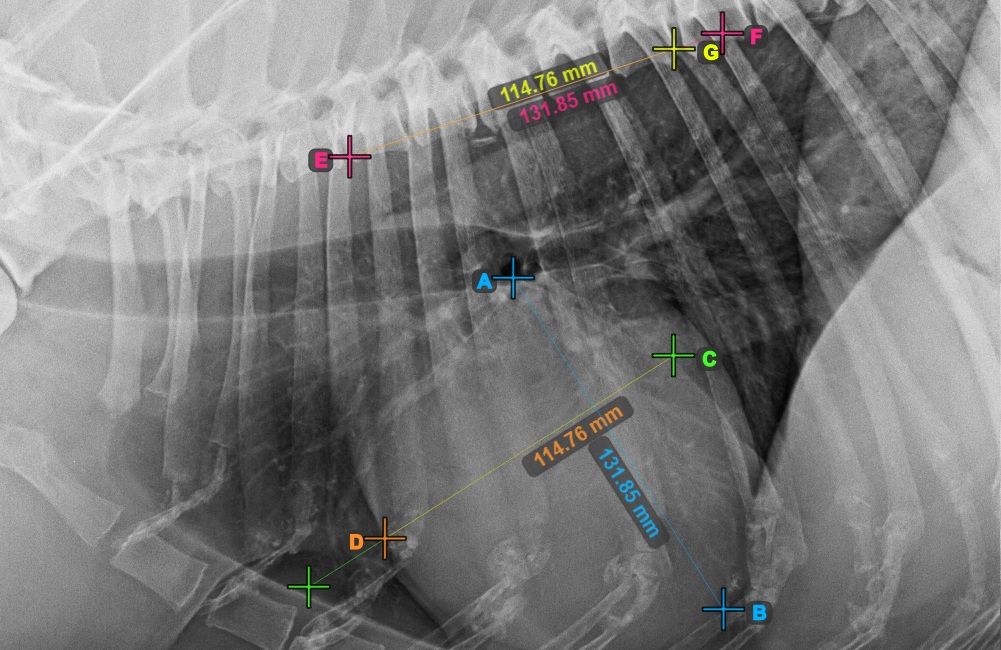

VHS - Herzmessung

VHS (Vertebral Heart Score) ist eine Messung, die in der Veterinärmedizin verwendet wird, um die Größe und Gesundheit des Herzens des Patienten zu beurteilen. Wählen Sie die VHS-Messung aus dem Erweiterten Messmenü und weisen Sie ihr die linke Maustaste zu.

Die VHS-Messung verwendet die Herzgröße im Vergleich zu den Wirbeln der Wirbelsäule, um kardiale Anomalien bei Patienten zu bestimmen und anzuzeigen.

Starten Sie die Messung, indem Sie die Bifurcatio tracheae in der Nähe der Herzspitze markieren.

Das Bild unten zeigt die typische Platzierung des Punkts Bifurcatio tracheae.